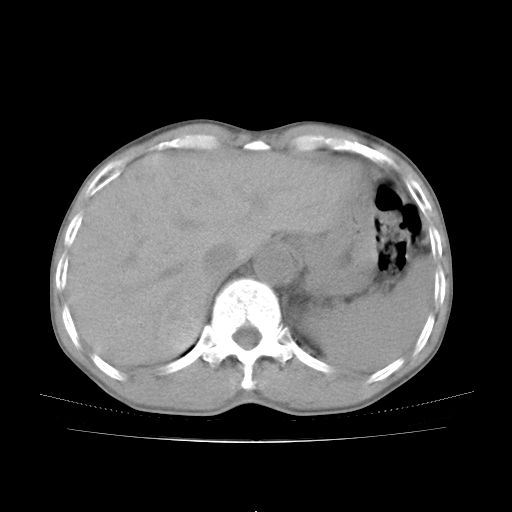

标题: CT25795:感冒后反复咳嗽两月余,痰中带血半月余。X诊断“肺 [打印本页]

标题: CT25795:感冒后反复咳嗽两月余,痰中带血半月余。X诊断“肺

1.双肺肺梗塞(理由:病灶呈三角形,与胸膜相连且局部胸膜肥厚,左心室增大)伴肺感染。

考虑两肺感染性病变,左肺上叶舌段肿瘤性病变待排;建议抗炎治疗后复查。